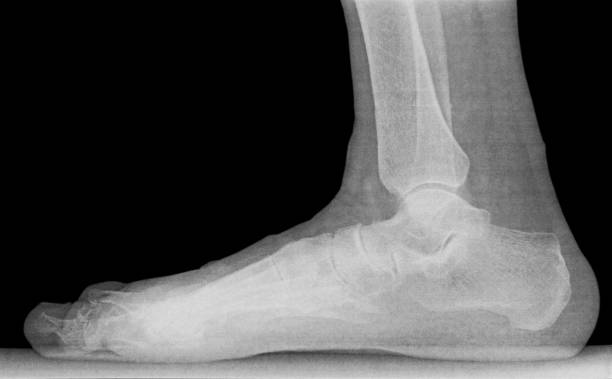

발뒤꿈치가 아픈 이유 첫 번째는 족저근막염입니다. 족저근막은 발뒤꿈치 뼈에서 시작하여 발바닥 앞쪽으로 연결되는 두껍고 강한 섬유질 띠입니다. 족저근막은 우리 몸의 중요한 역할을 하는데 아치 모양의 모양새는 우리 몸의 체중을 흡수하기 때문에 걷는 데 중요한 역할을 할 수 있습니다. 족저근막염은 이러한 족저근막에 반복되는 충격으로 근막을 둘러싸고 있는 콜라겐이 변성하면서 염증이 생긴 것을 의미합니다.

이러한 증상은 원래부터 평발이거나 걸음걸이나 생활습관 등으로 발이 변형되며 구조적으로 이상이 생겨서 문제가 생길 수도 있지만 기본적으로 하체 사용을 무리하게 하다보면 문제가 생기게 됩니다. 족저근막염 통증은 개인에 따라 다르지만 기본적으로 발뒤꿈치에 통증을 느끼게 되고 특히 아침 기상후 첫 걸음부터 통증이 나기 때문에 조기에 치료를 받는 것이 중요합니다.